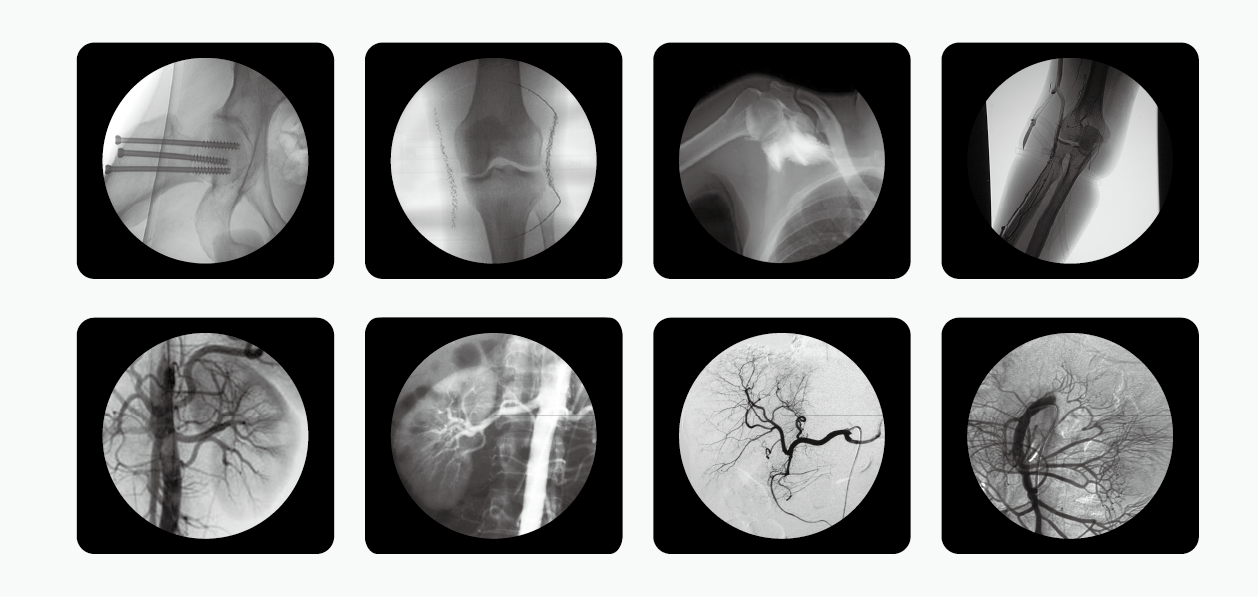

C型臂也就是我們所說的C臂機(jī)或C形臂X光機(jī)等,因?yàn)槠洫?dú)有的C型的機(jī)架而被這么命名,儀器主要由產(chǎn)生X射線的球管,采集圖像的影像增強(qiáng)器和CCD攝像機(jī),以及圖像處理的工作站組成,是現(xiàn)代臨床不可或缺的醫(yī)療輔助設(shè)備。

南京普愛醫(yī)療C形臂X光機(jī)是國內(nèi)眾多生產(chǎn)廠家中的一匹黑馬,該公司擁有多種型號的C形臂X光機(jī),其中PLX7000C被廣泛應(yīng)用于介入科、骨科、外科、矯形外科、泌尿外科、脊柱外科、腹部外科、疼痛科、心臟科、消化科、婦科及手術(shù)室等。

擁有更大功率的高壓發(fā)生器適合對肥胖病人的高密度組織進(jìn)行成像,并且也有更高熱容量的球館可以滿足長時間、大量手術(shù)的需要。多種工作模式,滿足各種臨床需要,多葉與垂直光影控制,有效減少軟X線,大幅降低皮膚劑量,其還配有進(jìn)口品牌影像增強(qiáng)器,全數(shù)字化CCD攝像機(jī),提供高分辨的優(yōu)質(zhì)圖像。

C形臂X光機(jī)PLX7000C整機(jī)性能如下:

1、數(shù)字化高頻發(fā)生器,采用微焦點(diǎn),利用射線劑量控制,滿足您的多種復(fù)雜臨床診治要求;雙面板人體圖形化液晶觸摸屏,操作智能快捷;雙運(yùn)動控制系統(tǒng)、雙曝光腳閘設(shè)計,極大滿足臨床操作;

2、全數(shù)字化百萬像素影像采集系統(tǒng),優(yōu)化設(shè)計和配置,為您提供高分辨率、高灰階圖像,支持您做出準(zhǔn)確診斷;

3、專用高清醫(yī)用液晶顯示系統(tǒng),呈現(xiàn)給您高亮度、高對比度的臨床圖像;對比自然,有益于診斷的圖像細(xì)節(jié)顯示更加清晰、層次更加豐富;

4、四維電動運(yùn)動控制,定位準(zhǔn)確,靈活自如;超大機(jī)架設(shè)計,提供了超大的診視空間,更加舒適的手術(shù)環(huán)境;全新設(shè)計,全新理念、帶來超凡體驗(yàn);

5、工作站具有大容量數(shù)字化存儲功能,透視和數(shù)字點(diǎn)片均以數(shù)字化格式無損存儲,邊緣增強(qiáng)多重鏡像 gamma校正、電影回放、窗寬窗位、專家模板、刻錄等強(qiáng)大處理功能。